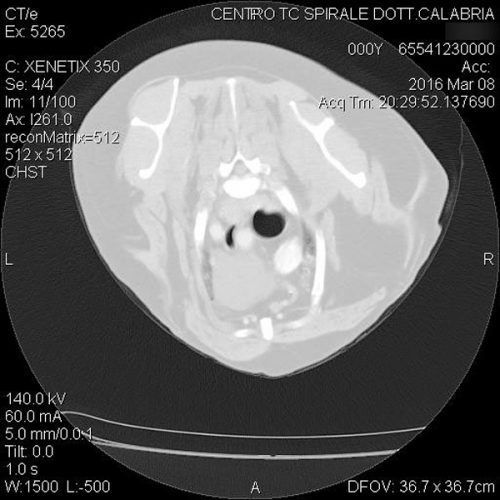

TC MULTISTRATO